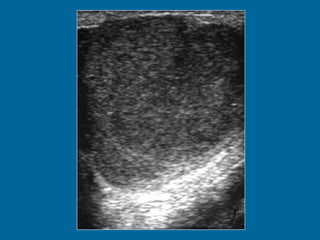

LINFOMA MALIGNO 1 a 8 % de los tumores testiculares. Pico de incidencia entre los 50 y 60 años de edad. Tumor testicular bilateral más común, sincrónico o metacrónico. 10% localizado al momento del diagnóstico (muy mal pronóstico). Ecografía Ecoestructura homogénea o heterogénea. Hipoecogenicidad. Degeneración hemorrágica y necrosis (raro). Afectación difusa con agrandamiento testicular. Nódulo o masa.

LINFOMA MALIGNO 1a 8 % de los tumores testiculares. Pico de incidencia entre los 50 y 60 años de edad. Tumor testicular bilateral más común, sincrónico o metacrónico. 10% localizado al momento del diagnóstico (muy mal pronóstico). Ecografía Ecoestructura homogénea o heterogénea. Hipoecogenicidad. Degeneración hemorrágica y necrosis (raro). Afectación difusa con agrandamiento testicular. Nódulo o masa.

Transverse US image of the left testis shows multiple hypoechoic lesions.

Transverse US imageof the left testis shows multiple hypoechoic lesions.